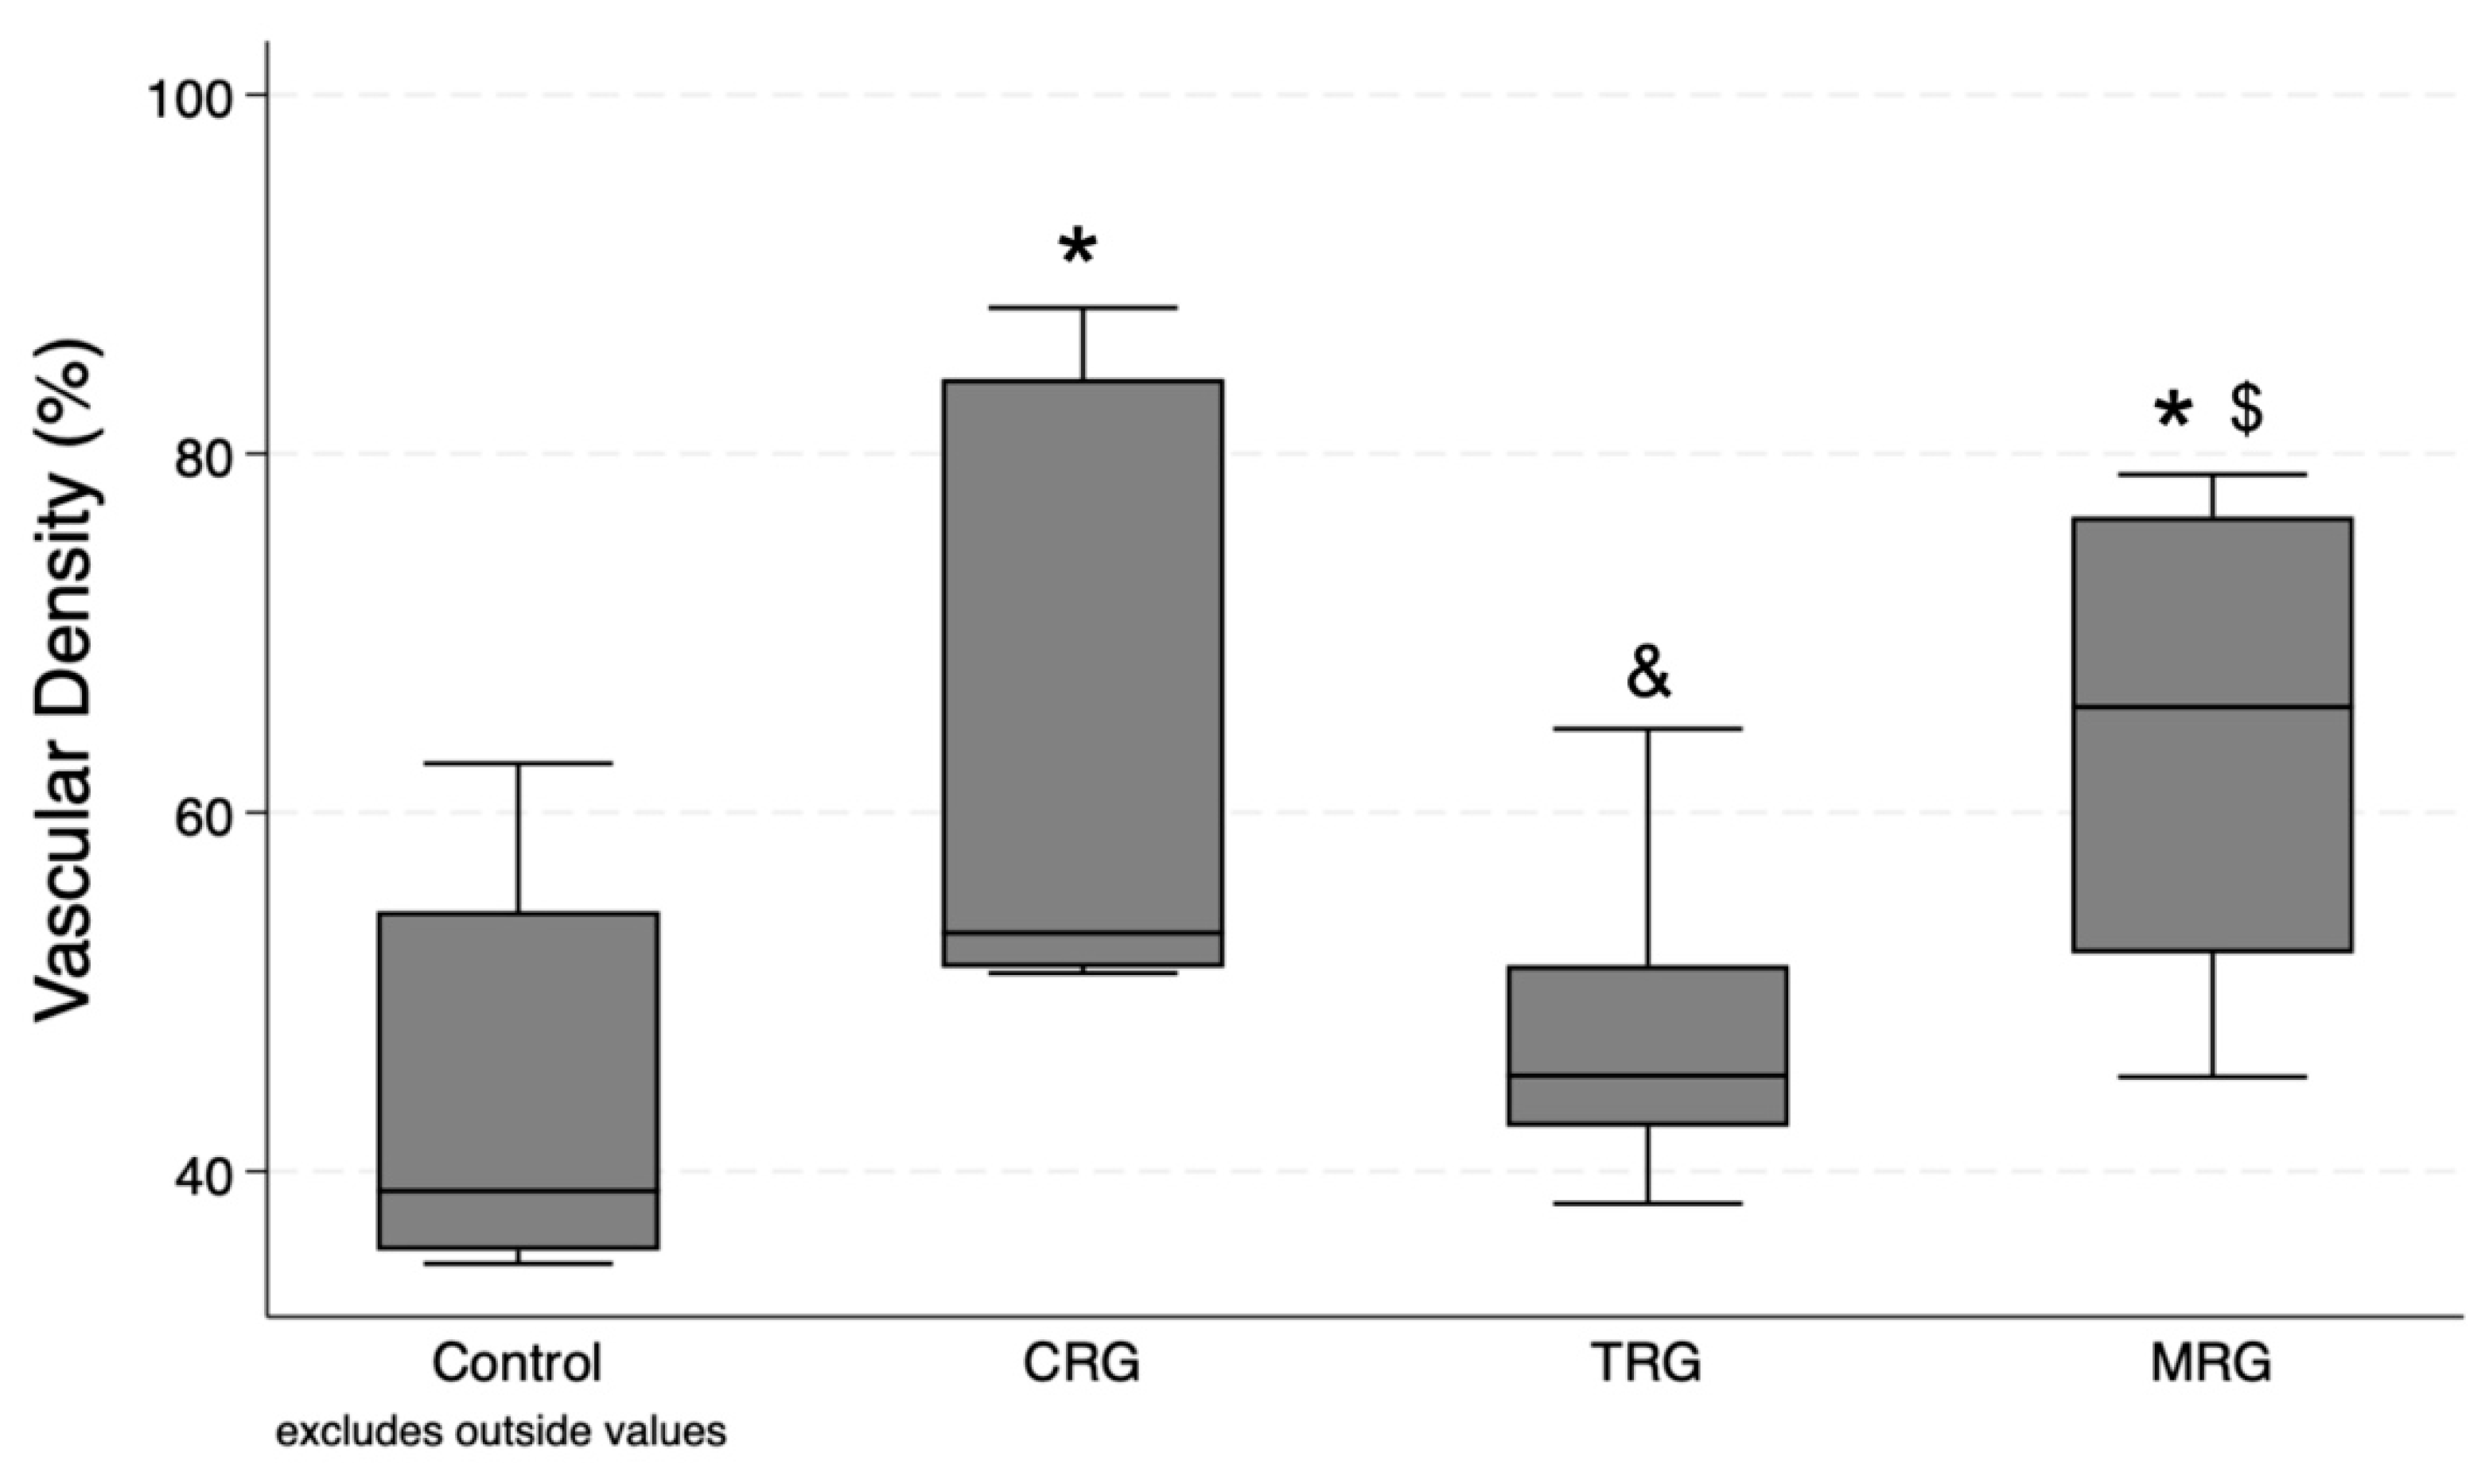

2.4. Vascular Density

3.3. Vascular Density

| Vascular density | 38.9 (35.59; 54.5) | 53.28 (51.34; 84.17) | 45.33 (42.5; 51.47) | 65.87 (52.15; 76.49) | 0.008 | CRG: 0.0062 TRG: 0.2579 MRG: 0.0019 | 0.032 | 0.3483 | 0.0125 |